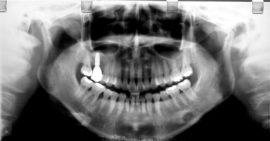

Przykład 1:

Podniesienie dna zatoki szczękowej. Prosty przypadek – pojedynczy brak.